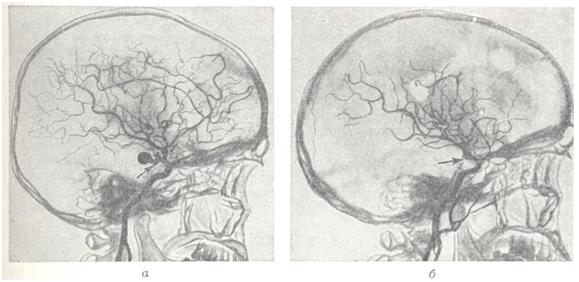

Рис. 2.

Большая мешковидная аневризма области бифуркации левой внутренней сонной артерии (ангиограммы): a — до операции; б — результат хирургического выключения аневризмы; видны клипсы на внутренней сонной артерии и аневризме, при ангиографии через правую сонную артерию хорошо заполняются сосуды как правого, так и левого полушария мозга.